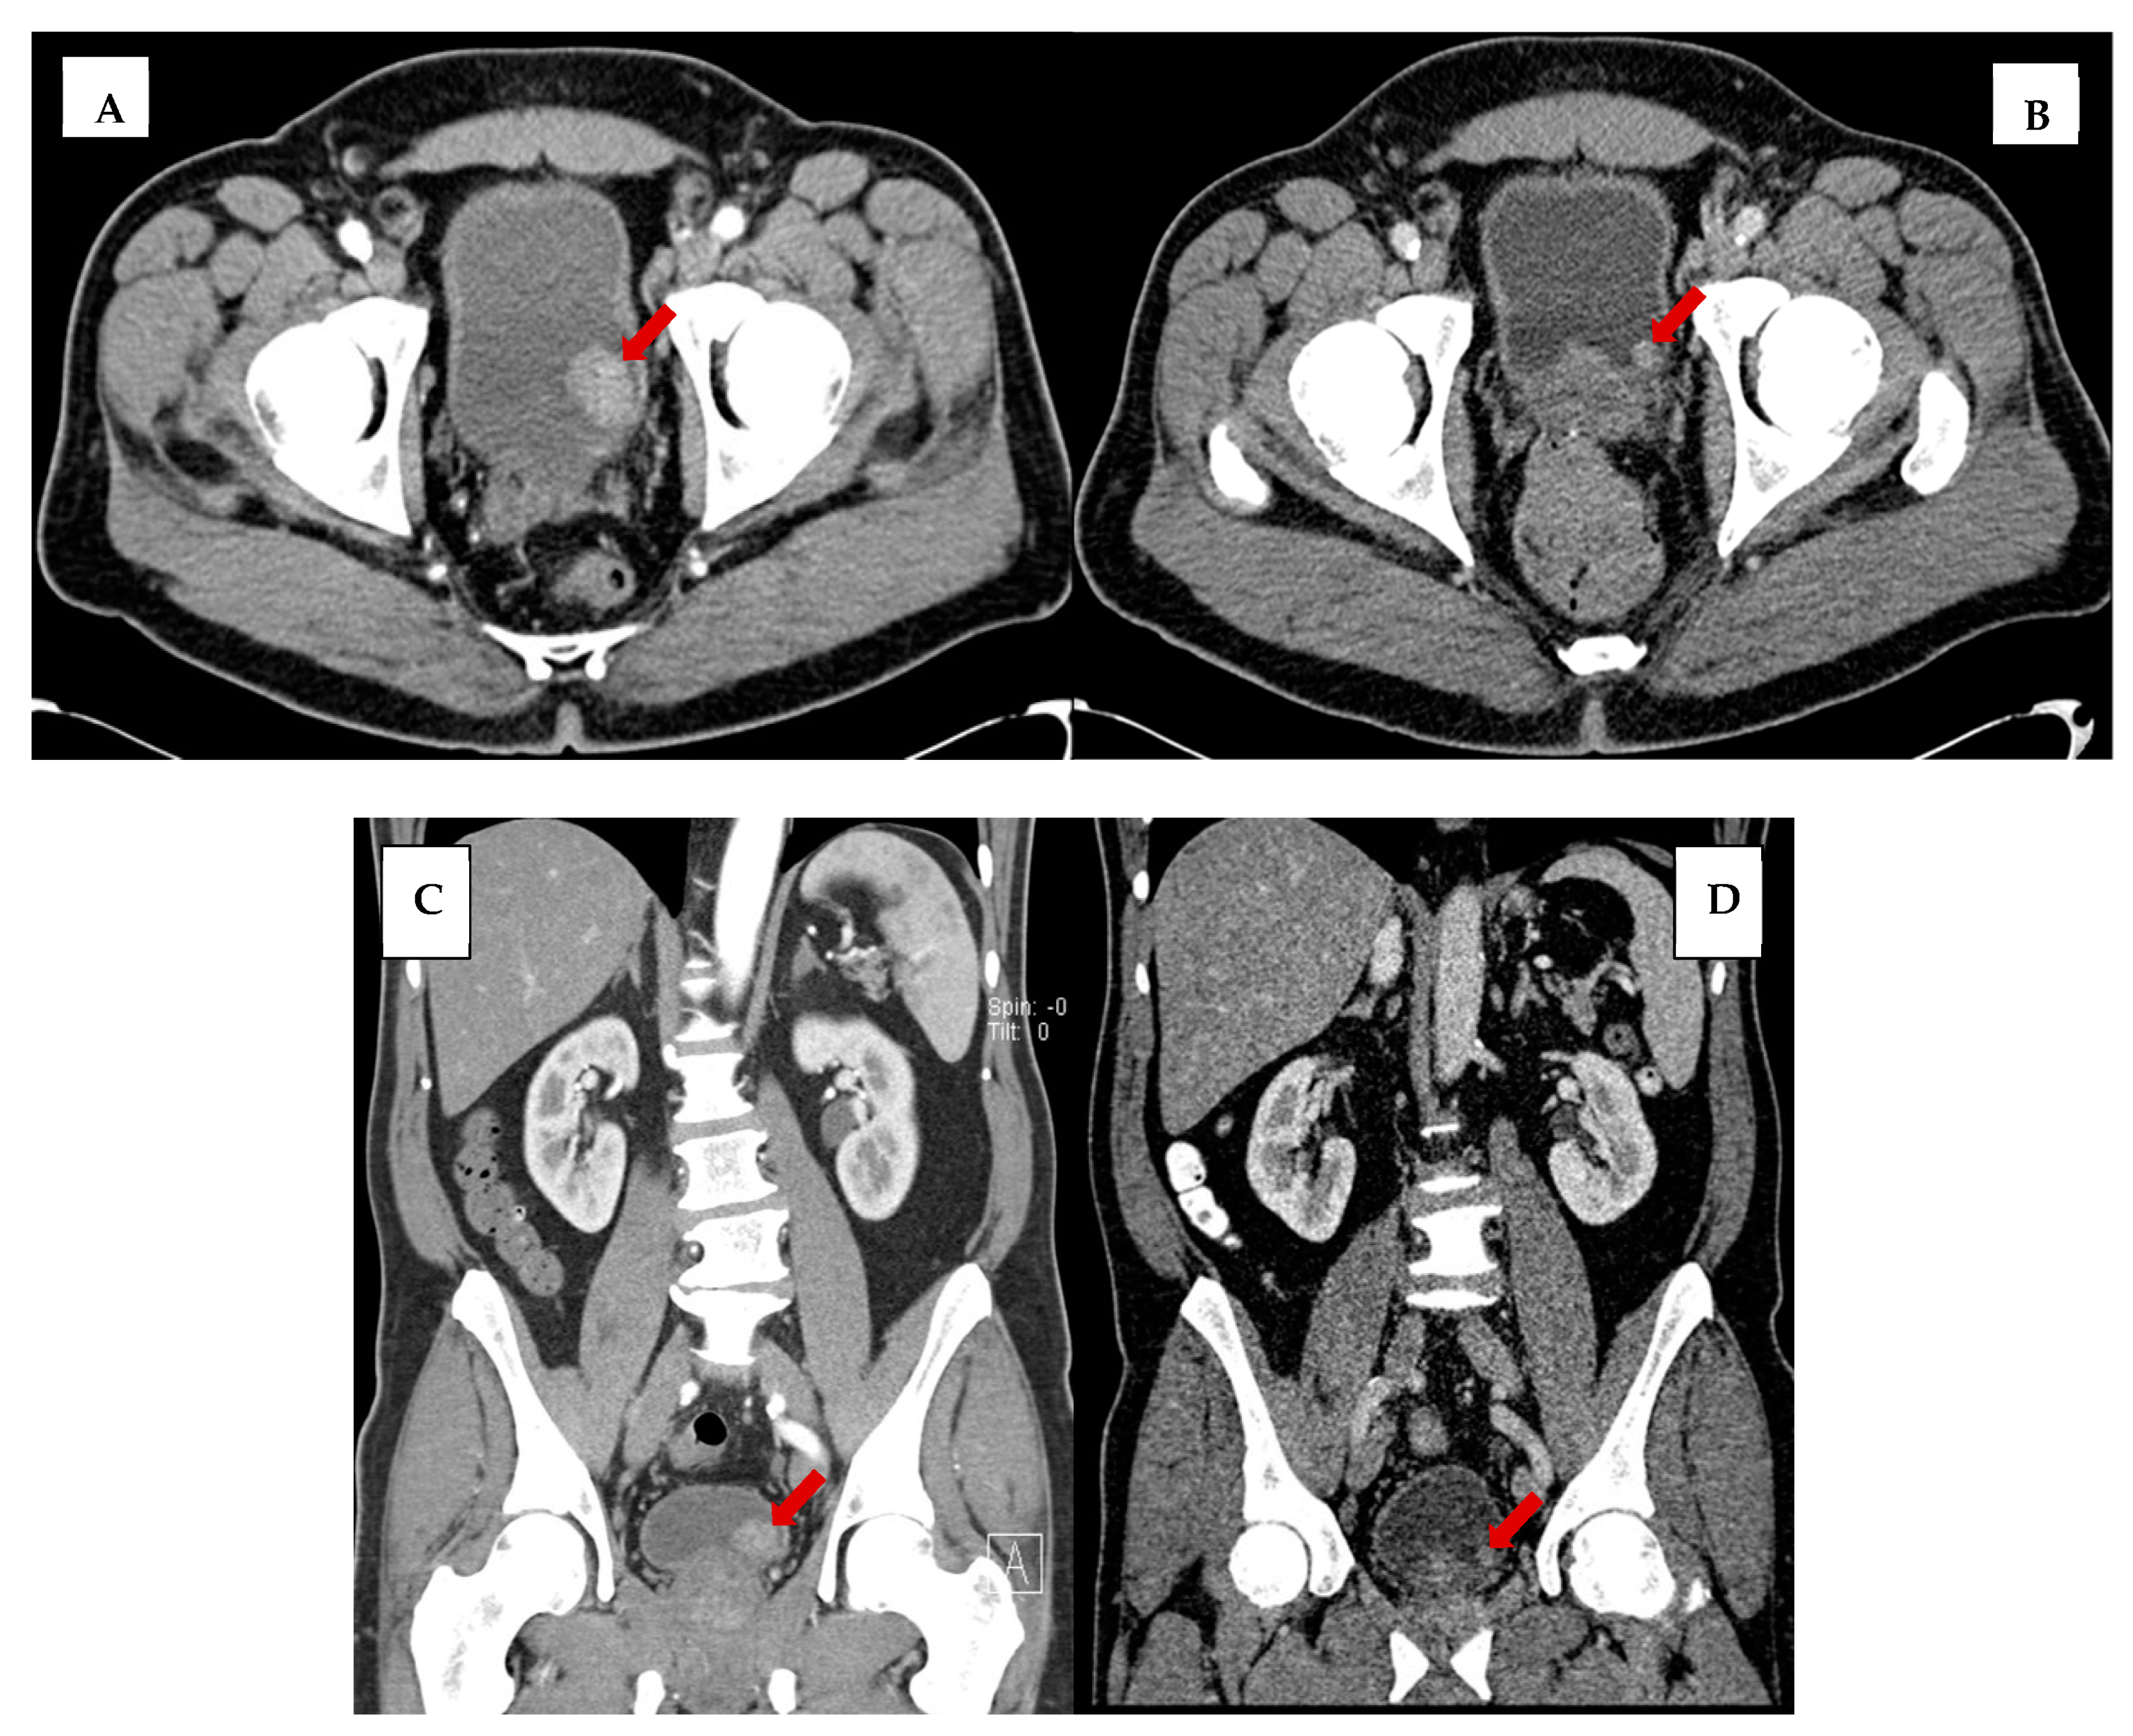

In a retrospective review of abdominopelvic CT imaging performed before a pathologically established diagnosis of non-muscle-invasive bladder cancer, we found that a bladder mass was discernable in over two-thirds of the patients, and in nearly one-third of the CT studies performed up to five years preceding the biopsy-confirmed diagnosis. Figure 5 is an illustration of one such example in a 62-year-old male who presented with left lower quadrant pain and hematuria and was worked up for bladder cancer with a CT of the abdomen and pelvis that showed a 2.6 cm intraluminal bladder tumor. In retrospect, a 1.0 cm bladder mass was present on a CT performed 2 years prior for diverticular disease. This highlights the need for the careful inspection of the urinary bladder wall in all abdominopelvic CT performed for any indication, and not merely those dedicated to evaluation of urinary tract symptoms.

Figure 5.

Axial view of bladder tumor (A) at time of bladder cancer diagnosis and (B) 2 years before diagnosis on imaging performed for diverticulosis. Coronal view of bladder tumor (C) at time of diagnosis and (D) 2 years before diagnosis. Red arrows to indicate bladder mass. Note the increased noise in images (B,D) secondary to dose reduction techniques.